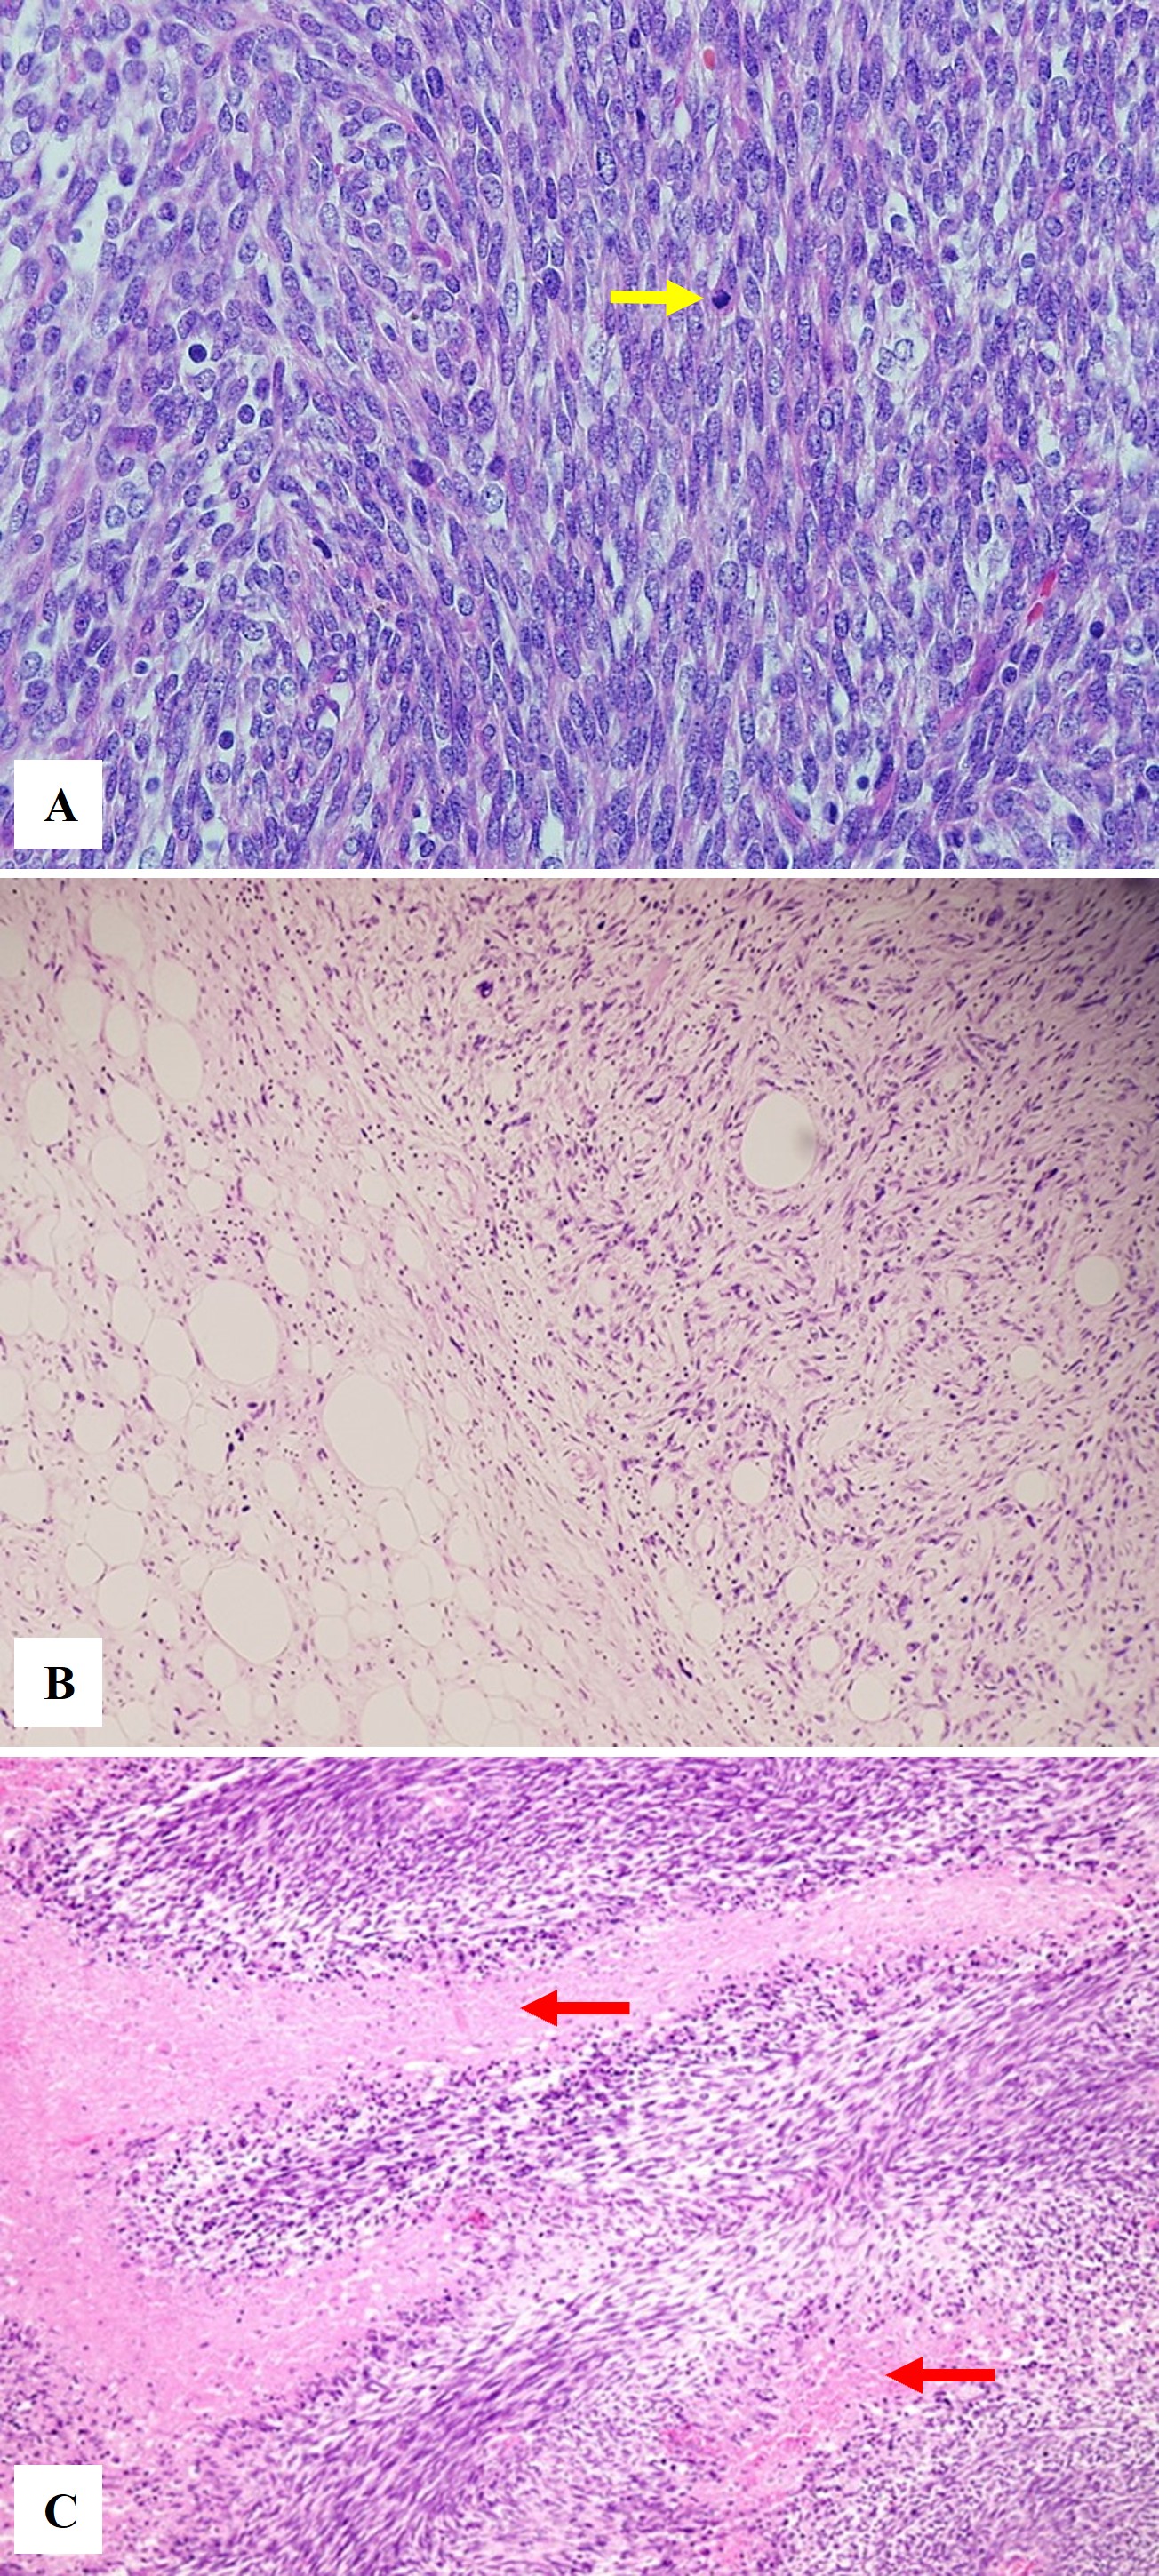

FIGURE 1: Conceptual framework